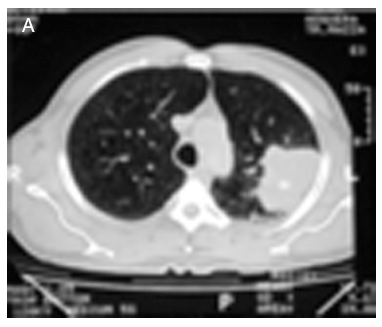

En el artículo titulado "Osteoartropatía hipertrófica secundaria a neoplasia broncogénica" (REV ESP REUMATOL 2004;31[7]:442-4) la figura 2A que aparece publicada no es correcta. Debería haberse publicado la que se representa a continuación.